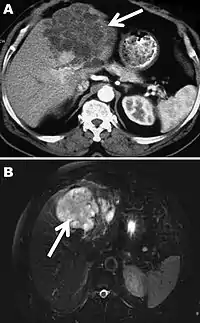

Інкубаційний період альвеолярного ехінококозу становить 5 — 15 років. Клінічний перебіг альвеококозу в перші місяці, а іноді й роки, майже безсимптомний. Надалі з'являються неприємні відчуття в ділянці печінки, ниючий біль, особливо під час бокових рухів. При цьому часто з'являється гарячка, нездужання, наростає втомлюваність. Найчастішою клінічною знахідкою є гепатомегалія (збільшення розмірів печінки). Спленомегалія (збільшення розмірів селезінки) виявляється лише у випадках, ускладнених портальною гіпертензією або тих, що пов'язані з метастазуванням альвеококових міхурів до селезінки. При проведенні ультразвукового дослідження виявляється пухлиноподібне утворення різного розміру в печінці. Здавлювання жовчних проток призводить до появи жовтяниці і холестазу, здавлювання печінкових вен — до появи асциту.

Діагноз альвеококозу підтверджується візуалізаційними методами діагностики та може бути підтверджений серологічними методами та / або молекулярною ідентифікацією Echinococcus multilocularis у зразках. Рекомендується двоступеневе серологічне дослідження, спочатку високочутливим тестом (гемаглютинація або імуноферментний аналіз з використанням гомологічного антигену, екстракту E. multilocularis), а потім провести вестерн-блот, який слід проводити у всіх випадках з високим рівнем підозри на основі візуалізації, особливо у пацієнтів з імунодепресією. Вестерн-блот-тести відрізняються високою чутливістю (97%), а перехресні реакції, що призводять до подібної картини, спостерігаються лише іноді в сироватках пацієнтів з нейроцистицеркозом. Остаточний діагноз покладається на патологію або ідентифікацію личинки паразита за допомогою молекулярної біології.